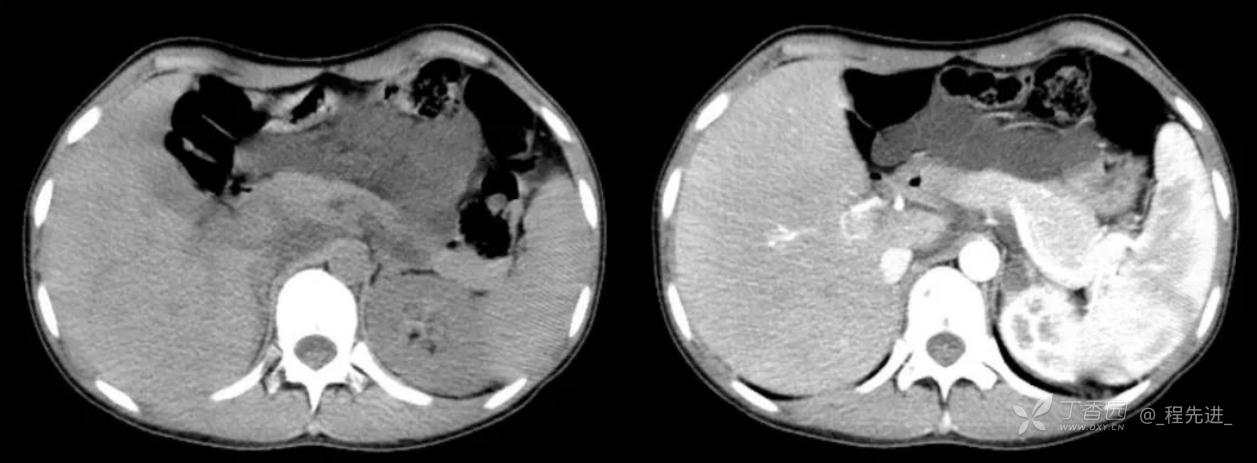

主诉:腹痛、发热一天

现病史:一天前无明显诱因出现腹痛并发热不适,伴恶心、干呕,诊所肌注药物(具体用药不详),无缓解,无明显尿频、尿痛。

体格检查:腹肌稍紧张,右上腹部轻压痛,右肾区叩痛